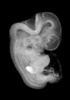

Carnegie Stage 18 (44 post-ovulatory days)

Most embryos at stage 18 are approximately 44 postovulatory days old and measure 13-17 mm in length. Distinguishing criteria for this stage include cervical and lumbar flexures, distinct notching in the hand plate, the first appearance of the elbow, eyelid folds may appear in more advanced specimens, and auricular hillocks begin to form distinct parts of the external ear.